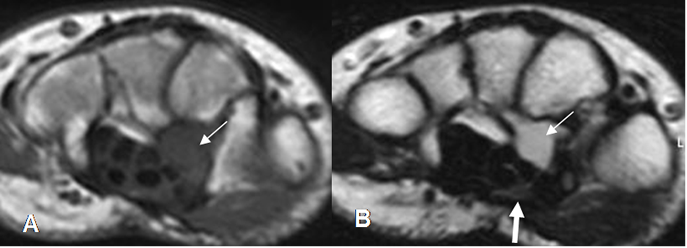

Fig 97. Neuropatía periférica.

A: RM axial en T1. Imagen redondeada e isointensa el músculo sobre la topografía del nervio mediano.

B: RM sagital en STIR. Lesión ovalada e hiperintensa a nivel de los metacarpianos, que tiene continuidad con el nervio mediano (Flecha gruesa) y corresponde a neurofibroma.